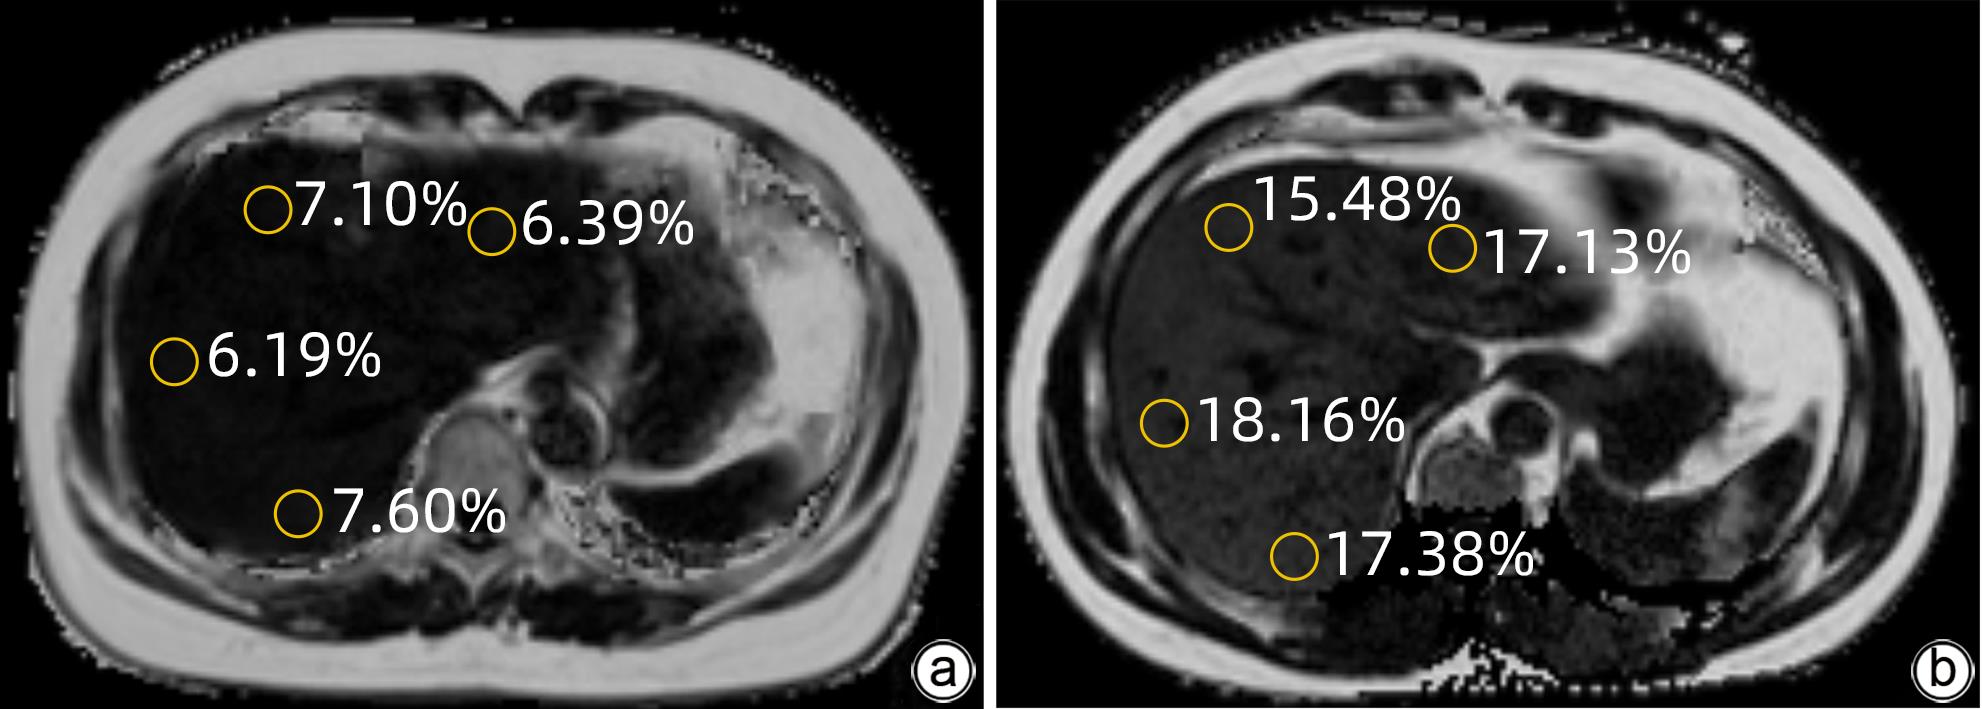

Application value of liver/spleen CT value, controlled attenuation parameter, and magnetic resonance imaging-proton density fat fraction in chronic hepatitis B patients with hepatic steatosis

Jingnan LU, Yansong LI, Ya WEN, Xionghui WANG, Zhaoyu QU, Jianlong LI, Wei ZHANG

2024, 40(1): 46-51. DOI: 10.12449/JCH240109

Abstract(1769) HTML (992) PDF (1052KB)(121)

Abstract:

Objective  To investigate the application value of liver/spleen CT value (CTL/S), controlled attenuation parameter (CAP), and magnetic resonance imaging-proton density fat fraction (MRI-PDFF) in chronic hepatitis B (CHB) patients with hepatic steatosis.  Methods  A retrospective analysis was performed for the clinical data of 213 CHB patients who underwent liver CT, CAP, and MRI-PDFF examinations in Affiliated Hospital of Yan’an University from October 2018 to December 2022. According to MRI-PDFF, the 213 patients were divided into CHB group with 111 patients (MRI-PDFF<5%) and CHB+hepatic steatosis group with 102 patients (MRI-PDFF≥5%), among whom there were 69 patients with mild hepatic steatosis and 33 patients with moderate to severe hepatic steatosis. The independent-samples t test was used for comparison of normally distributed continuous data between groups, and the Mann-Whitney U test was used for comparison of non-normally distributed continuous data between groups. The Bland-Altman plot was used to evaluate the consistency in MRI-PDFF measurement between two physicians. The Spearman’s correlation coefficient was used to analyze the correlation between CTL/S and MRI-PDFF and between CAP and MRI-PDFF. The receiver operating characteristic (ROC) curve was plotted and the area under the ROC curve (AUC) was calculated to investigate the value of CTL/S and CAP in the diagnosis of different degrees of hepatic steatosis, and the DeLong test was used to compare the AUCs of the two radiological examinations.  Results  MRI-PDFF had relatively high repeatability and stability in CHB patients. There is a significant negative correlation between CTL/S and MRI-PDFF (r=-0.800, P<0.001) and a significant positive correlation between CAP and MRI-PDFF (r=0.692, P<0.001). Both CTL/S and CAP had a relatively high accuracy in the diagnosis of hepatic steatosis in CHB patients, with an AUC of 0.951 and 0.902, respectively, and CTL/S had a better accuracy than CAP (P<0.05). In the diagnosis of mild and moderate-to-severe hepatic steatosis, CTL/S had an AUC of 0.921 and 0.895, respectively, and CAP had an AUC of 0.859 and 0.825, respectively, suggesting that CTL/S had a slightly higher diagnostic efficiency than CAP.  Conclusion  MRI-PDFF has high repeatability and stability in CHB patients, and CTL/S and CAP have a high diagnostic value for different degrees of hepatic steatosis in CHB patients.